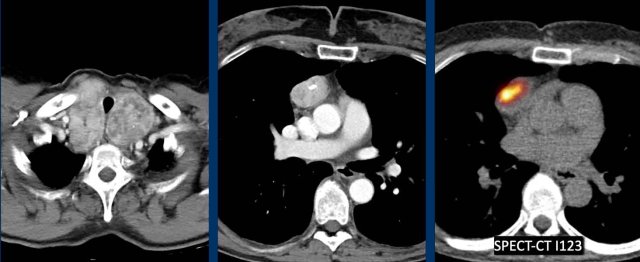

Ectopic thyroid

These images are of a 37-year old female.

She had a pneumonia and did not recover well and a CT was performed.

First study the images.

Question: what is the most likely diagnosis?

Images

There is a strong enhancing mass in the prevascular space.

Notice that it looks the same as the enhancing mass in the thyroid region.

Ectopic thyroid just looks like a goiter.

Sometimes there is a connection with the normal thyroid gland and sometimes the normal thyroid gland is absent.

You can proof the diagnosis with thyroid scintigraphy.

courtesy T. Mulders courtesy T. Mulders

Here a companion case.

There is a thyroid goiter and an enhancing mass in the prevascular space of the mediastinum.

I-123 is a radioisotope of iodine used for a thyroid uptake scan.

In this case the uptake is seen on a SPECT-CT.